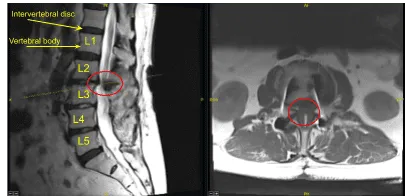

This patient had previously undergone an instrumented arthrodesis at an outside facility at L3-5. They presented with right anterior thigh and left posterior leg pain. Imaging displayed adjacent segment degeneration above and below her fusion mass which correlated well with her symptoms.